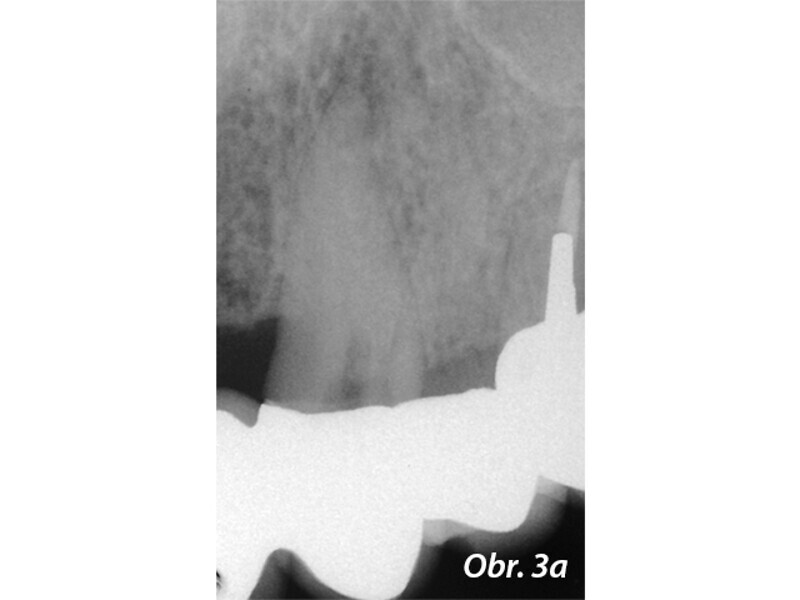

Aplikace MTA s použitím Produit Dentaires (PD) MAP System